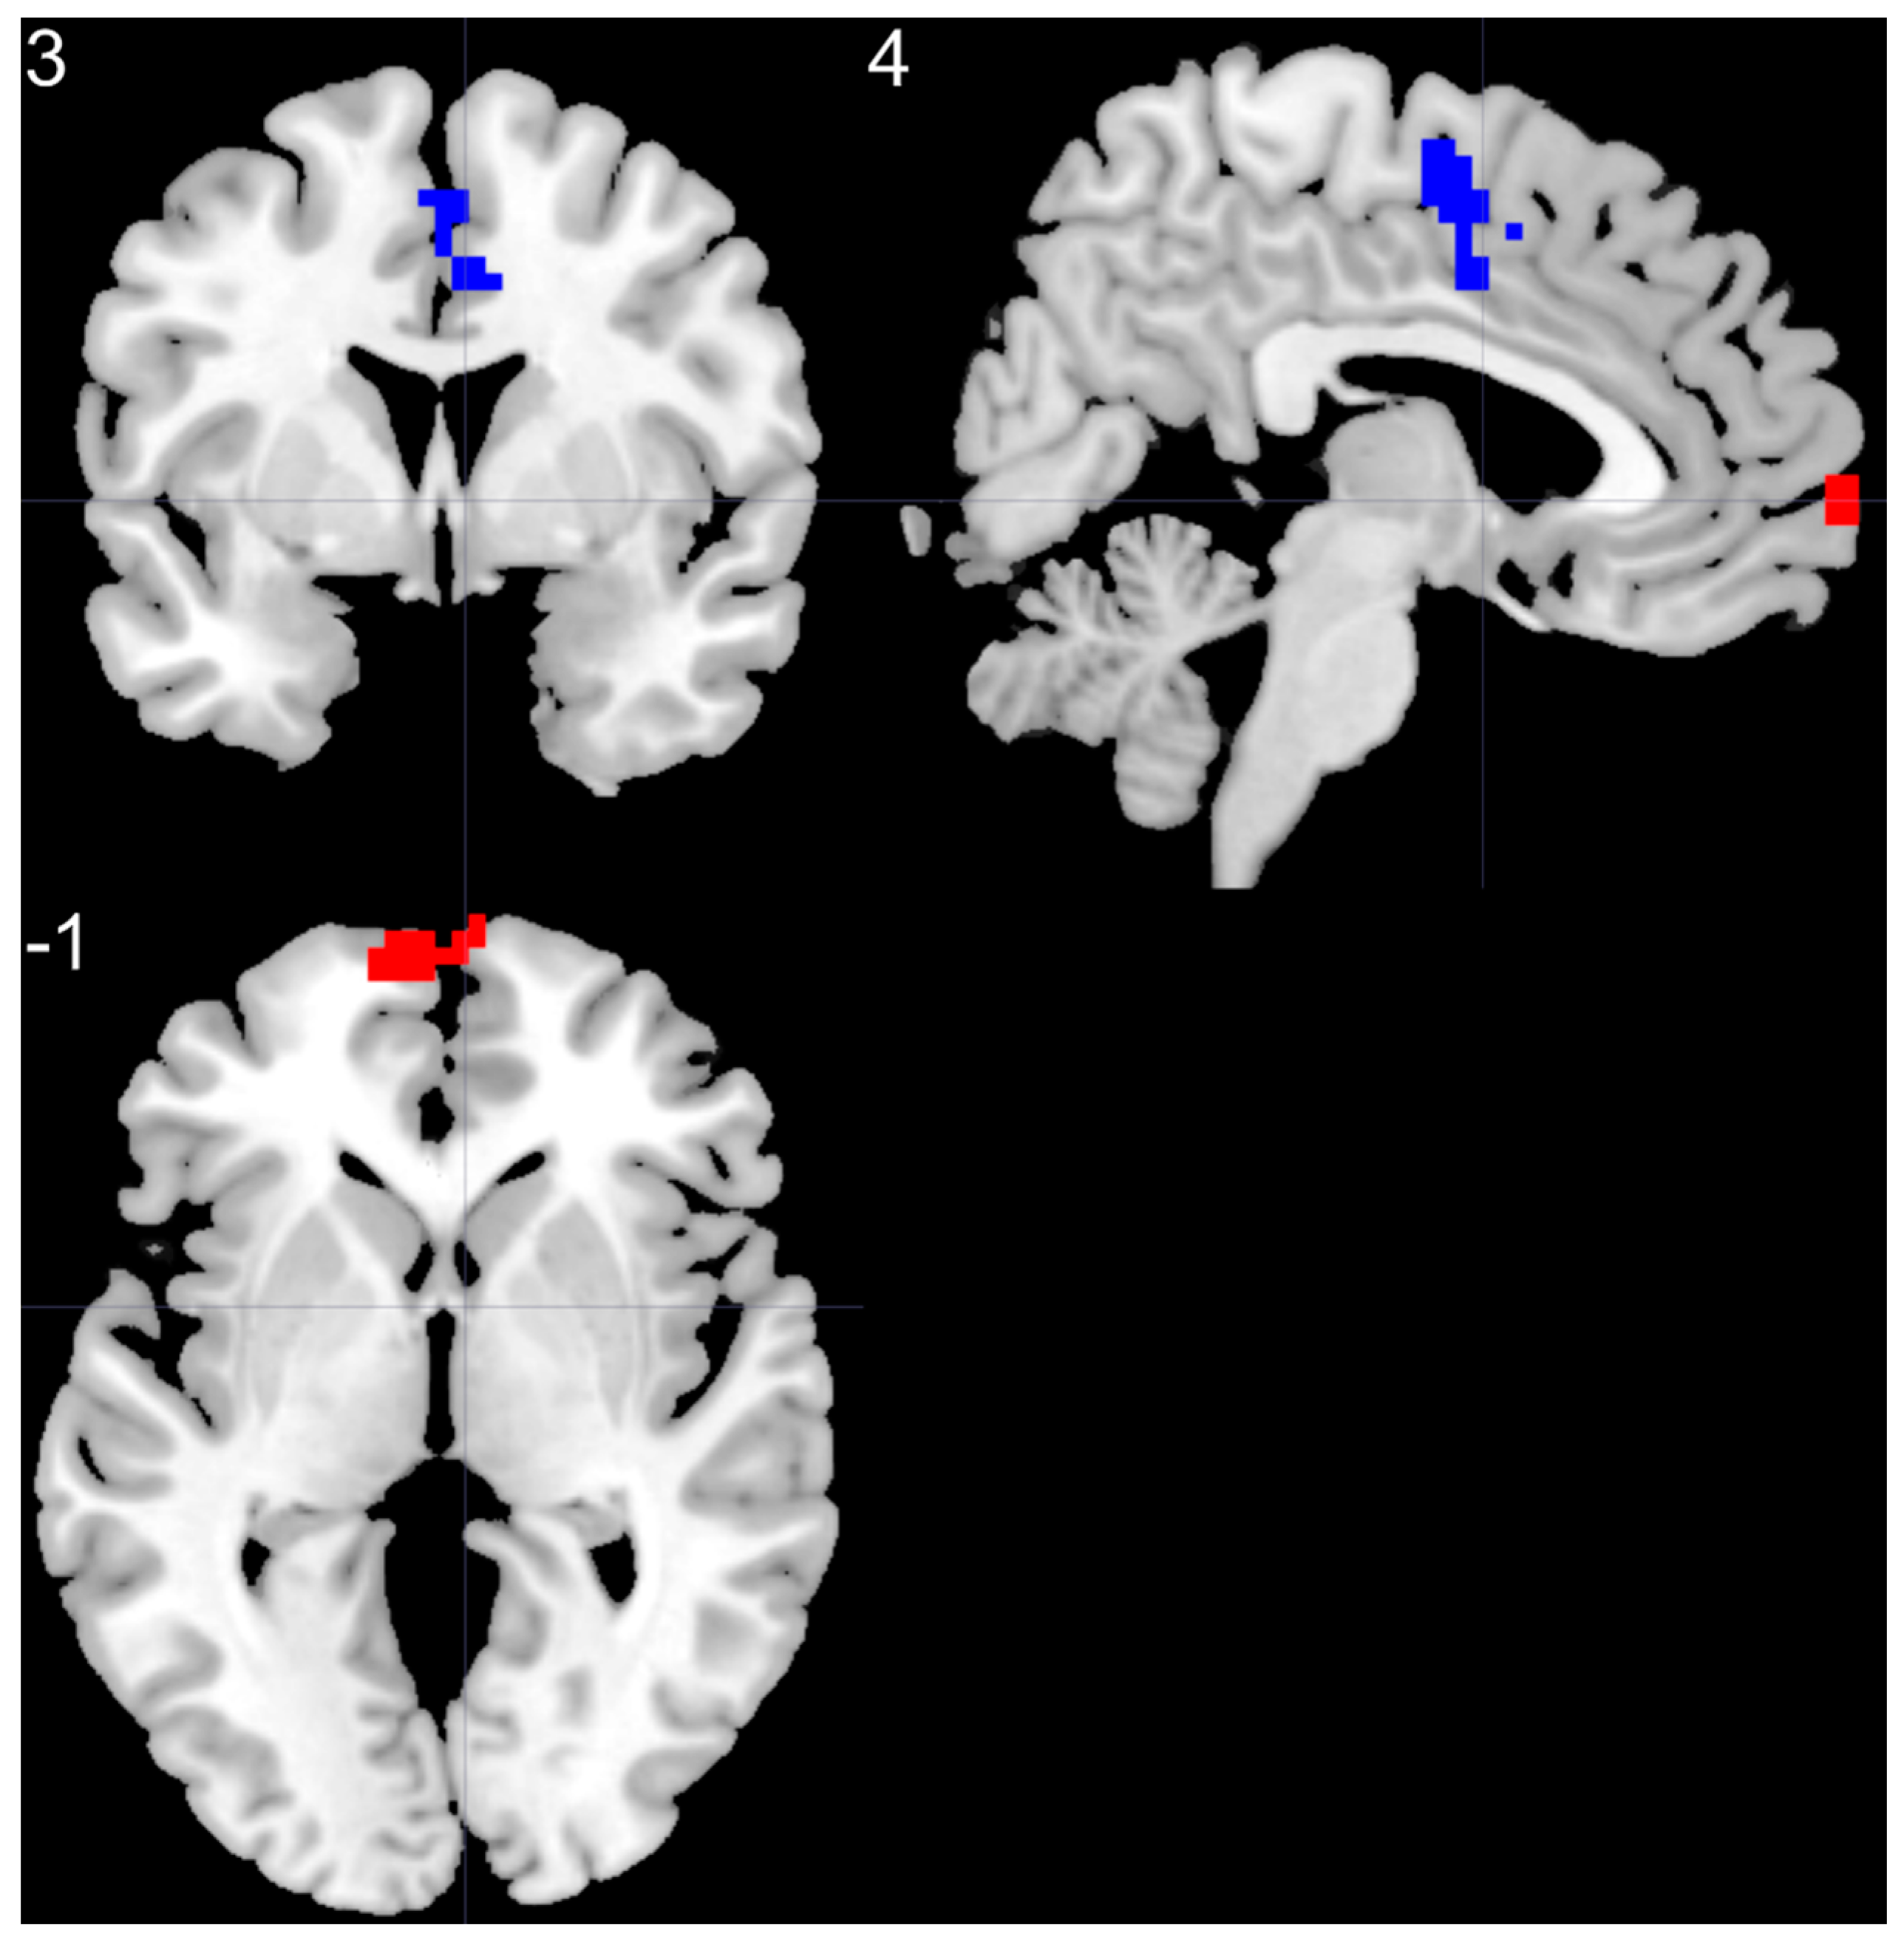

3.4. ALFF-Based FC Analysis

| Brain Regions | Peak T-Scores | MNI Coordinates | Cluster Size (Voxels) | ||

|---|---|---|---|---|---|

| x | y | z | |||

| BD > HC | |||||

| left SMF | 5.37 | −6 | 66 | 0 | 85 |

| BD < HC | |||||

| right SMA | −4.14 | 3 | −6 | 57 | 70 |